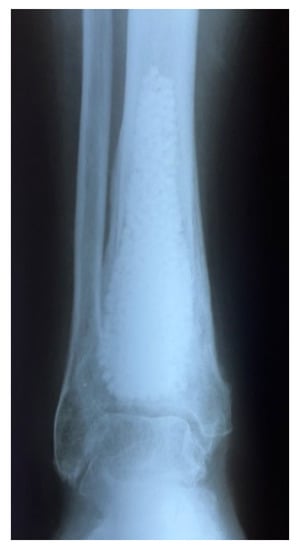

- Gómez-Barrena, E.; Rosset, P.; Gebhard, F.; Hernigou, P.; Baldini, N.; Rouard, H.; Sensebé, L.; Gonzalo-Daganzo, R.M.; Giordano, R.; Padilla-Eguiluz, N.; et al. Feasibility and safety of treating non-unions in tibia, femur and humerus with autologous, expanded, bone marrow-derived mesenchymal stromal cells associated with biphasic calcium phosphate biomaterials in a multicentric, non-comparative trial. Biomaterials 2019, 196, 100–108. [Google Scholar] [CrossRef]